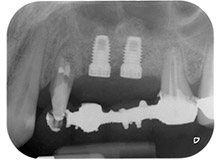

Un mois plus tard, le jour de l'intervention, la douleur et l'inflammation sur la dent 24 étaient minimes mais une mobilité de classe 2 de Miller était toujours observable. Après ouverture des lambeaux et nettoyage des tissus périapicaux et périradiculaires infectés, l'étendue du défaut osseux est devenue parfaitement visible (Figures 2 et 3).

À la racine de la dent, il manquait la totalité de l'os vestibulaire et distal. L'attache était essentiellement limitée à la racine palatine, venant ainsi confirmer le pronostic défavorable initial. La dent 27 présentait également une attache horizontale réduite et une raréfaction apicale minime (cf. Fig. 1), sans symptômes cliniques.